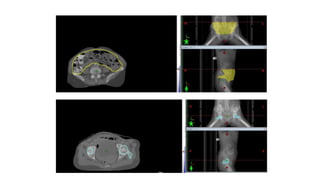

2. CTV NODAL:

1. Inguinal-femoral

2. Pelvic lymph nodes

(bilateral obturator and external and internal iliac)

Entire common iliac chain to the aortic bifurcation if pelvic

node positive

Proximal half of the posterior vaginal wall involved >>

pre- sacral LNs (from S1-S3).

INGUINOFEMORAL LYMPH NODES

First echelon lymphatic drainage>>

1. Superficial medial inguinal

2. Deep femoral lymph nodes.

• Anatomical compartment

• Laterally ----medial border of

the iliopsoas

• Medially ---- lateral border of

the adductor longus

• Posteriorly ----iliopsoas muscle

and pectineus

• Anteriorly ---edge of the

sartorius muscle and

rectus femoris

(Kim et al. 2012)

• #77 TILL THE APPEARANCE OF FEMORAL HEADS

• #78 7MM MARGIN AROUND THE VESSELS SHAVING OFF FROM THE BONE AND MUSCLES 1.5CM BRUSH JOINING EI AND II OBTURATOR LNS TILL THE VESSELS EXIT THE PELVIS OR THE UPPER BORDER OF THE OBTURATOR FORAMEN

• #80 is to the superficial medial inguinal and deep femoral lymph nodes.

• #81 space deep to the femoral vessels was not included in the CTV

• #82 The inguinal-femoral compartment should extend caudally approximately 2 cm from the saphenous-femoral junction or to the level of the lesser trochanter